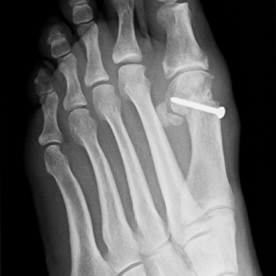

12) Hallux valgus

Häufigste und bedeutendste Zehendeformität mit seitlicher Abweichung der Großzehe im Grundgelenk. Es findet sich eine häufige Kombination mit einer Hammer- und Krallenzehe. Die konservative Therapie, meist im Frühstadium, umfasst die Druckentlastung des Großzehenballens, Barfußlaufen, ringförmige Schaumstoffpolster und Einlagenversorgung.

In fortgeschrittenen Fällen ist in der Regel eine operative Therapie mit Stellungskorrektur der Großzehe notwendig.